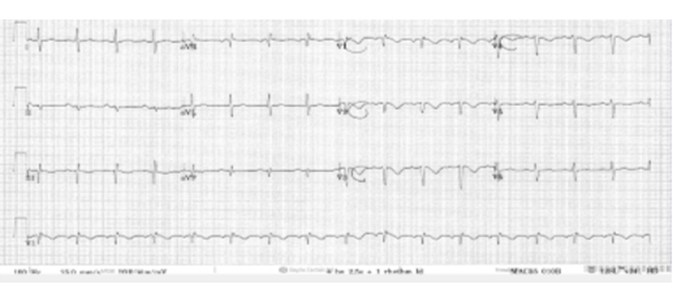

The lung fields appeared clear on chest X-ray (see Figure 1). Electrocardiogram (ECG) showed deep T wave inversion in leads III, V1 to V5 (see Figure 2). The first troponin was very elevated at 103.20 ng/L (normal reference range 0–13.9 ng/L) and the second troponin T taken after 4.5 hours was 119.20 ng/L. His C-reactive protein (CRP) was modestly elevated at 49 mg/L (normal reference range <5). His D-dimer was very elevated at 3499 ug/L (normal reference range <230 ug/L). A diagnosis of probable Non-ST Segment Elevation Myocardial Infarction (NSTEMI) with attendant acute pulmonary embolism (APE) was made.

Figure 2: 12 Lead ECG showing T-wave inversion in V1 to V3.